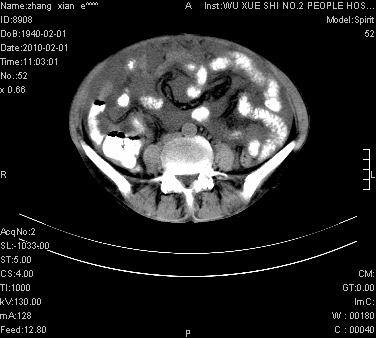

标题: CT24434:70岁 女 腹胀,腹水原因待查 [打印本页]

标题: CT24434:70岁 女 腹胀,腹水原因待查

腹盆腔大量积液,子宫增大,子宫颈增大外形不规则,内见低密度影,膀胱后壁显示不清,右腹股沟肿大淋巴结,脾脏囊性占位,子宫颈占位,子宫颈癌?建议增强。

子宫、宫颈占位?转移性腹水?肝性腹水?脾脏囊性占位,囊肿?血管瘤?淋巴瘤?

考虑:1、腹膜转移,大量腹水;

2、脾占位性病变;

3、左侧卵巢占位性病变,建议增强进一步检查。

大量腹水,右肾、脾囊肿可能性大          考虑左侧附件区占位,建议增强